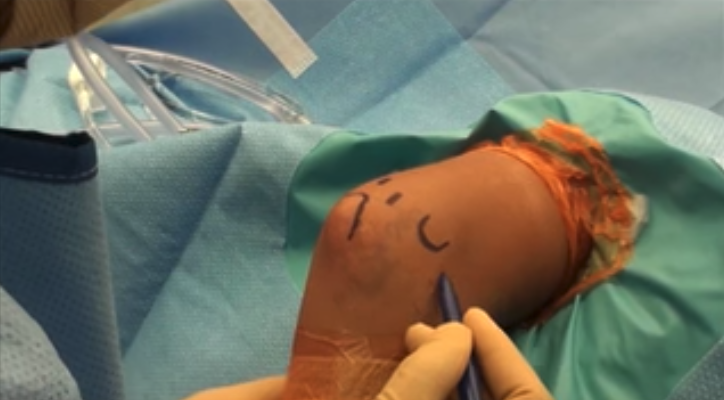

Red circle indicates that capitellum making contact with the radius bone. This figure also orients the next few scope images. The red circle is what the camera is visualizing.

A pin is used to make perforations in bone.

Perforations in the bone allow marrow elements to gain access to the defect and stimulate healing.